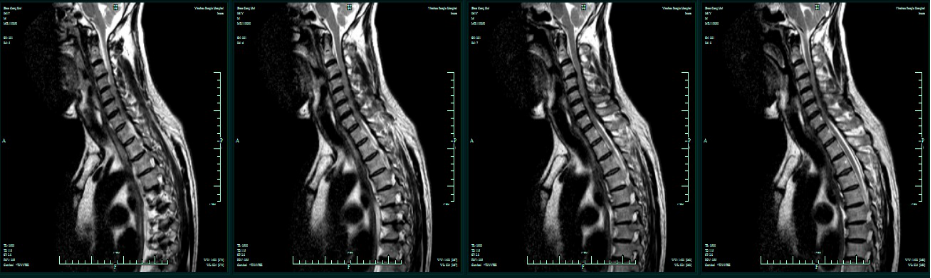

MRI增强:C4-T1椎管内髓外占位,淋巴瘤可能性大。

术前T2平扫

术前T1增强